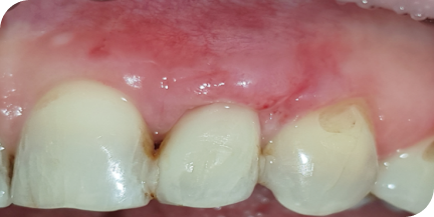

Случай из практики.

Лечение пародонтита

Пациентка (Ольга, 38 лет) обратилась в нашу клинику с жалобами на боль в дёснах, подвижность зубов, неприятный запах изо рта.

Мы провели полную диагностику. Диагноз — хронический генерализованный пародонтит средней степени тяжести. Выявлены проблемы: подвижность зубов 1-й степени, пародонтальные карманы более 5 мм, убыль костной ткани на 1/2 длины корня зуба.

Пародонтит — это воспалительные поражение окружающих тканей зуба, проникающее глубоко под десну. Воспаление вызывает разрушение костной ткани и связок зуба. На исходном фото это хорошо видно.

Провели консервативную пародонтологию и кюретаж зубодесневых карманов без разрезов и без швов.

Через 10 дней провели повторную чистку и полировку.

У пациента болей в десне больше нет, пародонтальные карманы отсутствуют, подвижность зубов отсутствует, убыли костной ткани больше нет, неприятный запах изо рта больше не наблюдается.

Исходное состояние